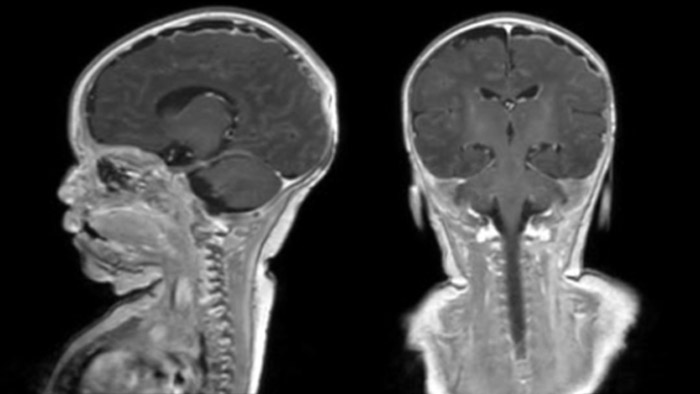

Dural sinus malformation (DSM) Initial examination

After three times of coiling and acryl based embolization

Rostral meningitis and arachnoiditis Both images are from the same 3D T1-weighted post contrast sequence in a newborn, under treatment.